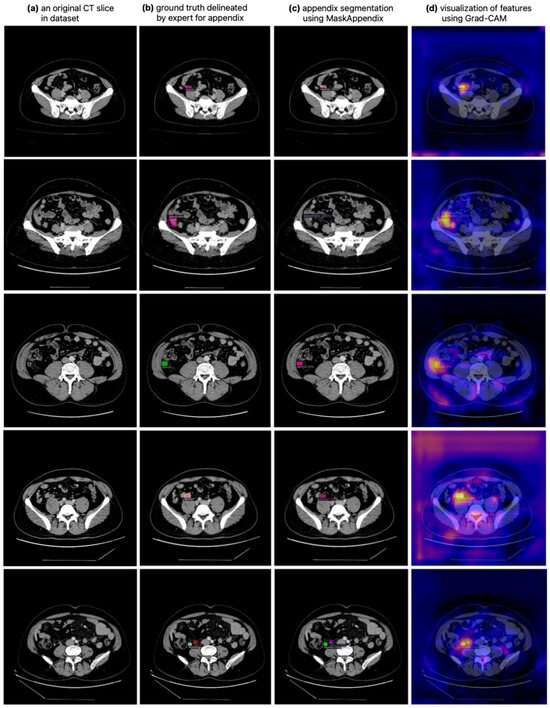

- The precise appendix segmentation on CT scans with localization is enhanced using Grad-CAM;

3.1. Results